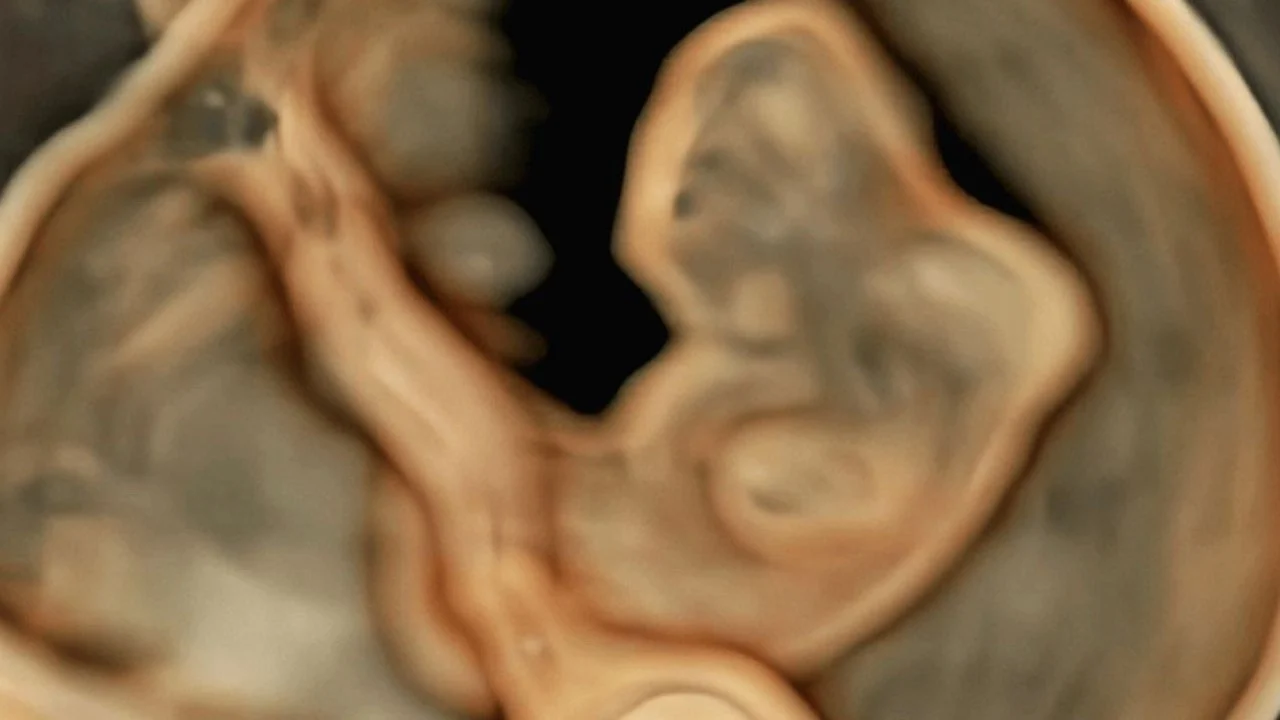

“On the cover of the November UOGJournal issue is a three-dimensional ultrasound image obtained using HDlive Silhouette mode, showing irregular cranial pole and absence of fetal brain vesicles in a fetus with acrania at 7 + 6 weeks’ gestation. Read the article by Meagher et al. for more case details here.”

Title: Early diagnosis of fetal acrania

Authors: S. Meagher, S. Christensen, W. Sepulveda, J. Ramkrishna